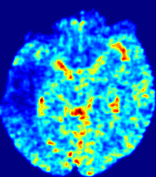

LesionRefer to captionRefer to captionRefer to captionRefer to captionRefer to captionRefer to caption𝐕rgbsubscript𝐕𝑟𝑔𝑏{\bf{V}}_{rgb}Refer to captionRefer to captionRefer to captionRefer to captionRefer to captionRefer to caption𝐕2subscriptnorm𝐕2{\|\bf{V}}\|_{2}Refer to captionRefer to captionRefer to captionRefer to captionRefer to captionRefer to captionRefer to caption3.53.53.52.82.82.82.12.12.11.41.41.40.70.70.70.00.00.0(mm/s)𝑚𝑚𝑠(mm/s)D𝐷DRefer to captionRefer to captionRefer to captionRefer to captionRefer to captionRefer to captionRefer to caption0.0200.0200.0200.0160.0160.0160.0120.0120.0120.0080.0080.0080.0040.0040.0040.0000.0000.000(mm2/s)𝑚superscript𝑚2𝑠(mm^{2}/s)Slice #1Slice #2Slice #3Slice #4Slice #5Slice #6

Figure 3: PIANO feature maps for one stroke patient, where the lesion is located in the left hemisphere. Top row: segmented stroke lesion region (white) on different slices, obtained from ISLES 2017. The corresponding slices for the PIANO feature maps are shown in the following rows.

For a better insight into an estimated velocity field 𝐕𝐕{\bf{V}} and diffusion field 𝐃𝐃{\bf{D}}, we compute the following maps: (1) 𝐕rgbsubscript𝐕𝑟𝑔𝑏{\bf{V}}_{rgb}: Color-coded orientation map of 𝐕=(Vx,Vy,Vz)T𝐕superscriptsuperscript𝑉𝑥superscript𝑉𝑦superscript𝑉𝑧𝑇{\bf{V}}=(V^{x},V^{y},V^{z})^{T}, obtained by normalizing 𝐕𝐕{\bf{V}} to unit length and mapping its 3 components to red, green, blue respectively; (2) 𝐕2subscriptnorm𝐕2\|{\bf{V}}\|_{2}: 222 norm of 𝐕𝐕{\bf{V}}; (3) D𝐷D: scalar field in Eq. 5.

Fig. 3 and Fig. 4 show the PIANO feature maps estimated from two ISLES 2017 patients: all are highly consistent with the lesion in both cases. Details of the blood flow trajectories are revealed in 𝐕rgbsubscript𝐕𝑟𝑔𝑏{\bf{V}}_{rgb} by the ridged patterns and the sharp changes of colors in the unaffected (right) hemisphere, while the flat patterns appearing within the lesion provide little directional information about the velocity and indicate low velocity magnitudes. Velocity magnitudes are more directly visualized via 𝐕2subscriptnorm𝐕2\|{\bf{V}}\|_{2}, from which one can easily locate the lesion where 𝐕2subscriptnorm𝐕2\|{\bf{V}}\|_{2} is low. D𝐷D also indicates lower diffusion values in the lesion, though with less contrast potentially due to the fact that it captures the accumulated effect of CA diffusion at the voxel-level.